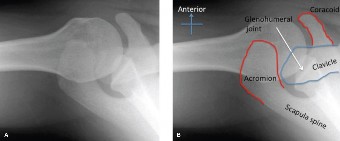

Rotator cuff tears are a common reason for shoulder pain and a common reason to obtain shoulder imaging. As a result, numerous different imaging modalities exist offering different pros and cons. Plain films are still the initial imaging modality of choice. These are most useful in ruling out other possible diagnosis but can help with the diagnosis of a rotator cuff tear as well. Changes to the tendon itself

may appear as calcific tendinosis, which would most commonly be seen at the bone–tendon interface. A decrease in the acromiohumeral distance (less than 2 mm) may also be indicative of a cuff tear. In late cases of rotator cuff tears, superior subluxation of the humerus may be evident. Certain variations in acromial anatomy, including spurs or a hook-shaped (type 3) acromions, may be associated with rotator cuff tears as well. With progression of rotator cuff tears, degenerative changes including spurs, cysts, and sclerosis may be evident at the greater tuberosity. In late, massive tears one may see degenerative changes consistent with rotator cuff arthropathy.

Shoulder CT scans (Answer A) are not typically used to diagnose rotator cuff tears. X-rays, aka roentgenograms (Answer C), can show signs of rotator cuff pathology but are not diagnostic. Some signs of chronic rotator cuff tears that are sometimes seen on AP view x-rays include calcific tendonitis, calcification of the coracohumeral ligament, proximal migration of the humerus, and cystic changes of the greater tuberosity. An outlet view x-ray can show a type III (hooked) acromion, which is correlated with a higher rate of rotator cuff tears, or an OS acromiale, which would require special consideration for surgical treatment. Shoulder arthrograms (Answer D) are used primarily only when MRI is contraindicated and are considered positive for a rotator cuff tear if dye leaks from the glenohumeral joint into the subacromial space. MR arthrogram (Answer E) has been shown to have equivalent diagnostic ability compared with standard MRI and can be used to diagnose rotator cuff tears. However, it adds an additional step and cost to a standard MRI, and it does not offer any additional diagnostic benefit for rotator cuff pathology. Therefore, standard MRI is preferred to MR arthrogram.